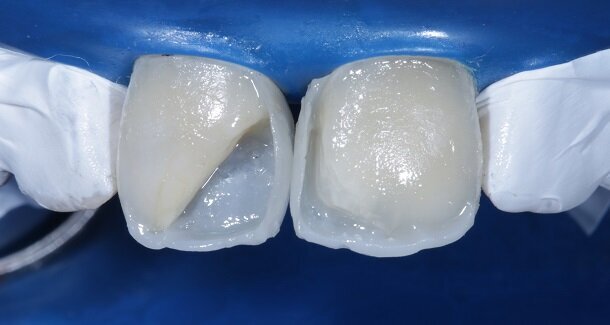

The figures show the clinical work flow involved. In the 1st appointment Oral prophylaxis, oral hygiene instructions were followed by an impression that was sent to the lab for a wax up [Fig 3 and 4]. In the subsequent appointments, Endodontic treatment was followed by Intra and extra coronal office bleaching using the Pola office bleaching kit. After two weeks, the shade stabilised post bleaching. Shade selection, rubber dam isolation and preparation was done on both the teeth to receive Direct composite veneers so as to close the midline diastema as well as correct the fractured teeth and the slight mal-alignment. Controlled Body Thickness (CBT) technique of layering was used with 3M Z350XT shades - Dentin shades A3, A2 and Enamel shades A2, clear translucent [Figures 5 to 11]. This was followed by the Finishing and polishing protocol as described in the figures.

Characterisation begins during Dentin Layering itself. [Fig 9] Shape of the tooth is extremely important. A well-made putty key from a wax-up or a mock-up can help in maintaining shape of the tooth. [Fig 3 and 4]